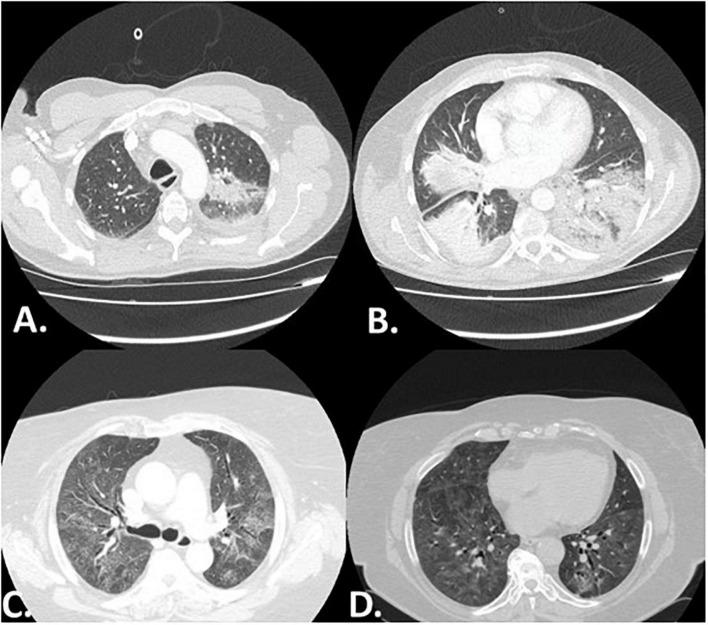

We identified 75 patients with myositis associated-ILD. Median age (95% CI) at the time of diagnosis was 64.0 (61.0-65.0) years. Antinuclear antibody testing was positive in 40% of the cohort ( = 30/75). Myopathy onset occurred first in 40.0% of cases ( = 30), ILD without evidence of myopathy occurred in 29 patients (38.7%), while 16 patients (21.3%) were diagnosed concomitantly with ILD and myopathy. The commonest radiographic pattern was cellular non-specific interstitial pneumonia (NSIP) and was observed in 29 patients (38.7%). The radiographic pattern of organizing pneumonia was significantly more common in patients diagnosed with the amyopathic subtype compared to patients that presented with myopathy [24.1% ( = 7/29) vs. 6.5% ( = 3/46), = 0.03]. One year survival was 86.7% in the overall population. Kaplan-Meier analysis demonstrated significantly higher all-cause 1-year mortality in patients with the amyopathic subtype compared to patients with evidence of myopathy [H R 4.24 (95% CI: 1.16-15.54), = 0.03]. Patients diagnosed following hospitalization due to acute respiratory failure experienced increased risk of 1-year all-cause mortality compared to patients diagnosed in outpatient setting [HR 6.70 (95% CI: 1.19-37.81), = 0.03]. Finally, patients with positive anti-MDA5 presented with higher 1-year all-cause mortality compared to anti-MDA5 negative patients [HR 28.37 (95% CI: 5.13-157.01), = 0.0001].

Specific ILD radiographic patterns such as NSIP and organizing pneumonia may herald underlying inflammatory myopathies. Hospitalized patients presenting with bilateral organizing pneumonia refractory to antibiotics should be meticulously evaluated for myositis associated-ILD even if there is no overt muscular involvement. Incorporation of ILD radiological patterns in the diagnostic criteria of inflammatory myopathies may lead to timely therapeutic interventions and positively impact patients' survival.

我们确定了75例肌炎相关ILD患者。诊断时的中位年龄(95%CI)为64.0(61.0 - 65.0)岁。40%的队列(n = 30/75)抗核抗体检测呈阳性。40.0%的病例(n = 30)肌病首发,29例患者(38.7%)出现无肌病证据的ILD,而16例患者(21.3%)同时诊断为ILD和肌病。最常见的影像学模式是细胞性非特异性间质性肺炎(NSIP),29例患者(38.7%)出现此模式。与有肌病表现的患者相比,诊断为无肌病亚型的患者中机化性肺炎的影像学模式明显更常见[24.1%(n = 7/29)对6.5%(n = 3/46),p = 0.03]。总体人群1年生存率为86.7%。Kaplan - Meier分析表明,与有肌病证据的患者相比,无肌病亚型患者1年全因死亡率显著更高[HR 4.24(95%CI:1.16 - 15.54),p = 0.03]。因急性呼吸衰竭住院后诊断的患者与门诊诊断的患者相比,1年全因死亡风险增加[HR 6.70(95%CI:1.19 - 37.81),p = 0.03]。最后,抗MDA5阳性的患者与抗MDA5阴性的患者相比,1年全因死亡率更高[HR 28.37(95%CI:5.13 - 157.01),p = 0.0001]。

特定的ILD影像学模式,如NSIP和机化性肺炎,可能预示潜在的炎性肌病。即使没有明显的肌肉受累,对于出现双侧机化性肺炎且对抗生素治疗无效的住院患者,也应仔细评估是否为肌炎相关ILD。将ILD影像学模式纳入炎性肌病的诊断标准可能会导致及时的治疗干预,并对患者的生存产生积极影响。